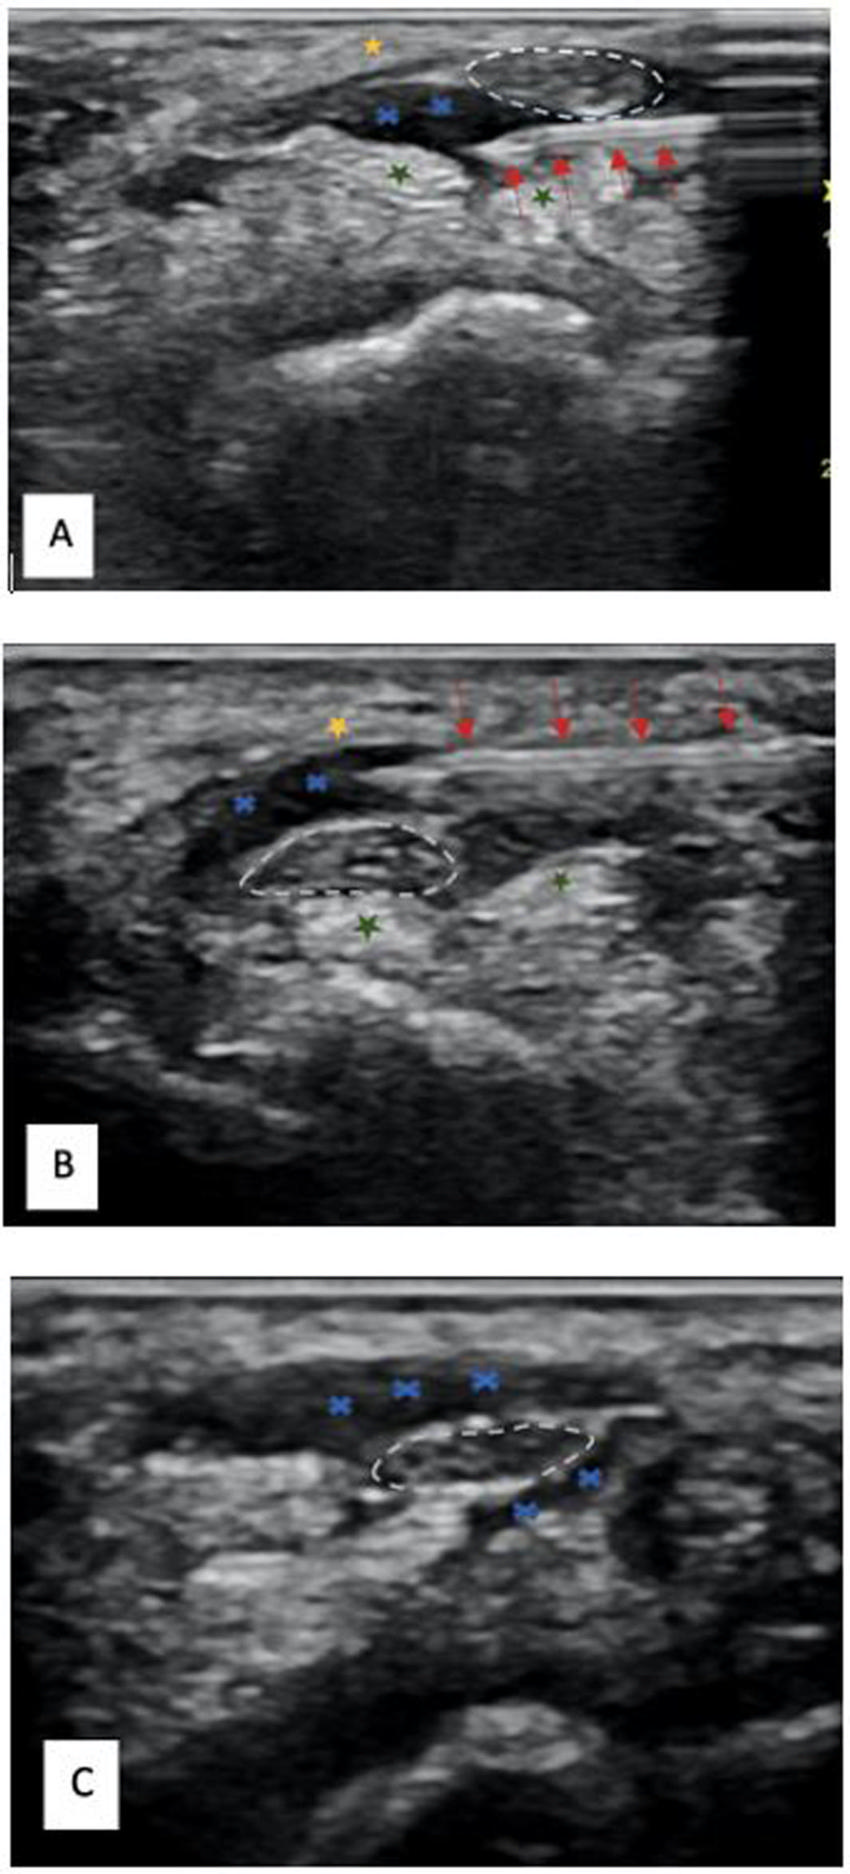

Figure 1. Ultrasound images depicting hydrodissection procedure in a patient with carpal tunnel syndrome. (A) Needle placed below the median nerve with fluid dissecting the nerve from the underlying flexor tendons (green star). (B) Needle placed above the median nerve with fluid dissecting the nerve away from the flexor retinaculum (yellow star). (C) Image at completion of procedure depicting the dissected median nerve with fluid all around. Red Arrow - needle, Blue cross -hydrodissection fluid, white dashed lines - median nerve.

High-res (TIF) version